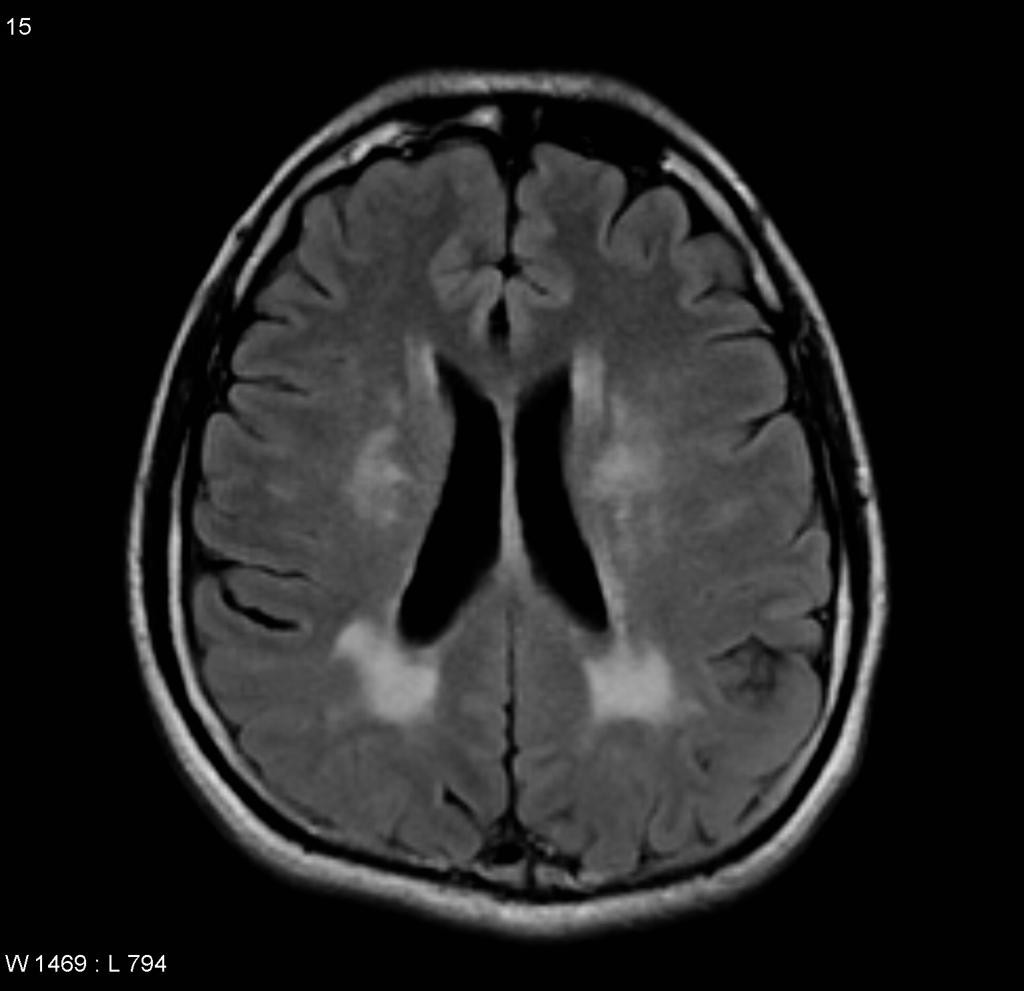

CADASIL

• Cerebral Autosomal Dominant Arteriopathy with Subcortical Infarcts and Leukoencephalopathy

• Artériopathie cérébrale autosomique dominante avec infarctus sous-corticaux et leucoencéphalopathie

• Démence vasculaire héréditaire

• Atteinte de la substance blanche des lobes temporaux et des capsules externes en plus du reste de la SB déjà atteinte dans la leucoaraiose